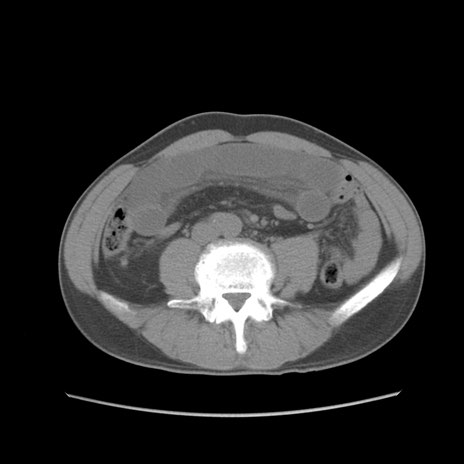

症例56 CT(横断像)

脂肪ウインドウ